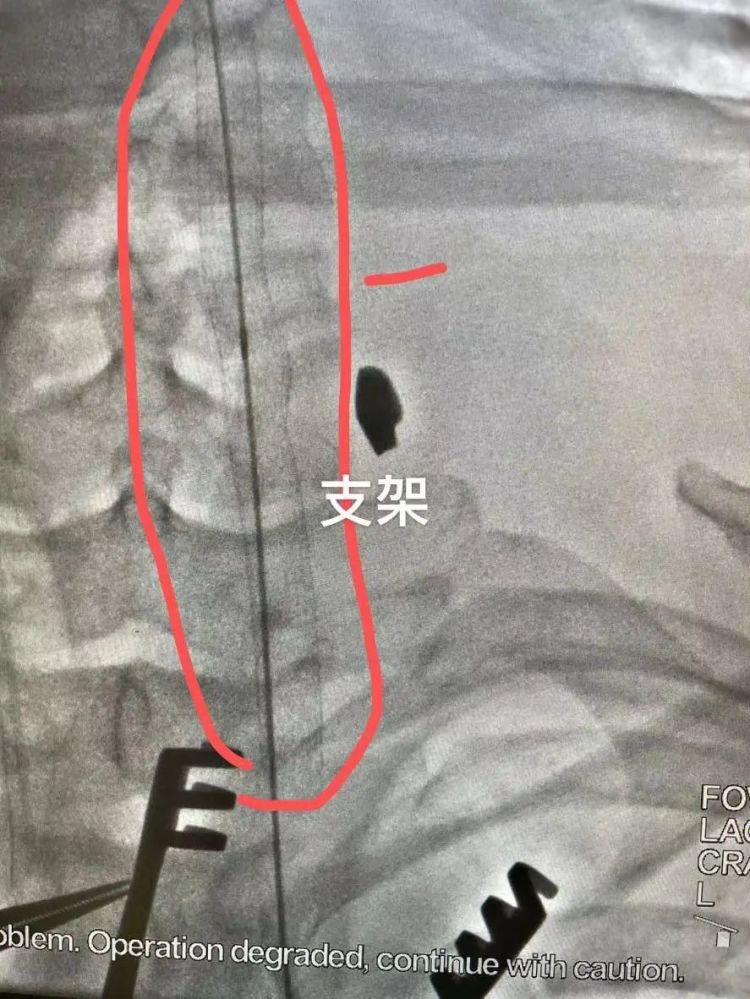

颈动脉破损处形成的假性动脉瘤

根据陈先生的病史和术前CT影像,赵文军手术团队迅速制定好了手术方案。“分两步走,先用支架从里面堵住血管破损处,再从颈部开刀进去修补血管 。”

使用的支架,全称是人工血管覆膜支架,从大腿根部处通过穿刺血管置入,送到颈动脉破损处。这是介入手术范畴,需要医学影像引导,杂交手术室为患者节约救命时间的优势这时就显现出来了。

当支架在陈先生颈部顺利打开,相当于给颈动脉穿了一件“内甲”,完美堵住了出血口。

“外围血肿清除后,能看到长约1厘米的颈动脉破口,还能看到里面的人工血管覆膜支架。”赵文军说,手术视野清晰,能让外科医生更快速地完成缝合。